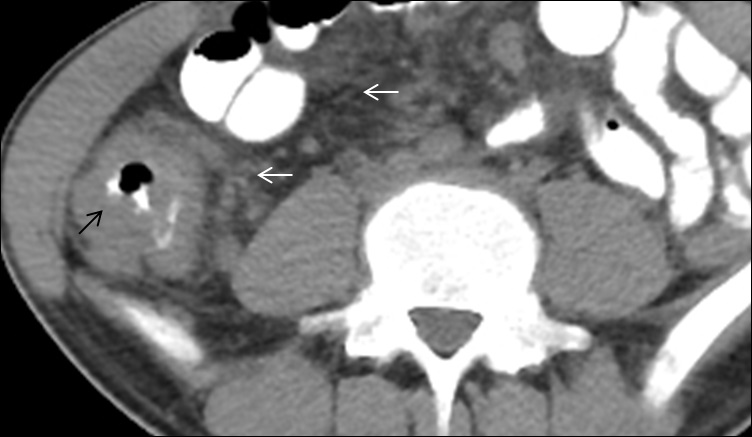

Primary intestinal involvement in tuberculosis is uncommon. The gastrointestinal involvement occurs through ingestion of infective organism with sputum or food via hematogenous route or direct spread from the adjacent organ. Tuberculosis is the infection which can involve any segment of the gastrointestinal tract and in colon it forms coccon formation (Figure 3) and the ileocaecal valve, terminal ileum and caecum are found to be more commonly involved; in approximately 90% of intestinal tuberculosis (Figure 4A,4B), it cal also involved colon part as one of our patient has ascending colon thickening and came out to be tubercular (Figure 5). Rectal involvement in tuberculosis is also rare, which represents fistula formation or fibrosis with rectal inflammation. Clinical presentations of rectal tuberculosis are hematochezia and constipation.

Major imaging findings seen in the intestine are symmetrical or asymmetrical bowel wall thickening, fistulae, altered enhancement, or mesenteric fat stranding and strictures are seen in chronic infection. A pulled up caecum is seen into the right subhepatic space due to retraction of the surrounding mesentery. A conglomeration of findings such as asymmetry of the ileocecal valve, the cecal wall thickening, intra-caecal absorption of the terminal ileum, along lymphadenopathy is evocative of tuberculosis [4]. When tuberculosis is suspected, a surgical biopsy should be done to establish the diagnosis.

Figure 3: A 40 years old female presented with abdominal distension and pain. On the venous phase of post-contrast computed tomography in the axial plane, thick enhancing peritoneal membranes (white arrow) were noted covering the clumped up bowel loops (thick black arrow). A mild amount of loculated fluid and free air is also present in the abdominal cavity (thick white arrow). There are classical features of the abdominal cocoon with perforative peritonitis, for which the patient underwent surgery. Intraoperative findings were labeled as a whitish cocoon-like sac encasing the bowel loops. Excision of cocoon-like fibrous tissue was done, followed by an abdominal rising. Excised tissue was sent for histopathological examination and found out to have tubercular bacilli in it. The patient started on anti-tubercular treatment and presently doing fine.

Figure 4: (A,B) A 25 years old lean and thin female presented with disturbed bowel habits and pain abdomen with on & off fever from last few months. A contrast-enhanced computed tomography scan in the axial plane (A & B) demonstrate thickening of the terminal ileum, ileo-caecal junction and caecum, causing lumen obliteration with surrounding mesenteric fat stranding (white arrow). After colonoscopy guided biopsy, it was proven to be intestinal tuberculosis. The patient had a standard four-drug regimen of ATT for six months, and after that, she was symptoms free.

Figure 5: A 45 years old female presented with pain abdomen and chronic diarrhea. A contrast-enhanced computed tomography axial image from the venous phase demonstrates circumferential thickening of ascending colon (black arrow) with adjacent fat stranding (white arrow). Diagnosis of colonic TB was made through endoscopy guided biopsy. The patient received antitubercular drugs and is recovering well.